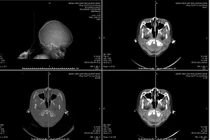

Các bác sĩ đã khẩn trương thăm khám, làm các xét nghiệm và chụp CT sọ não. Kết quả ghi nhận hình ảnh tụ máu dưới màng cứng bán cầu phải, kèm phù não.

Bệnh nhân được chẩn đoán chấn thương sọ não tụ máu dưới màng cứng. Bệnh nhân được chỉ định điều trị nội khoa tích cực, truyền dịch, dùng kháng sinh, thuốc an thần, giảm đau, chống phù não và tăng tuần hoàn não.